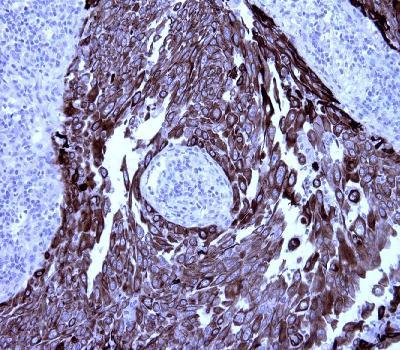

Mouse Monoclonal Antibody to CK5 (CK-HMW)(Clone :BS42)(Discontinued)

Figure-1: Lung squamous cell cancer section has been stained using CK5 antibody (Clone: BS42) with 1:200 dilution. Lung squamous cell cancer stained intensively.